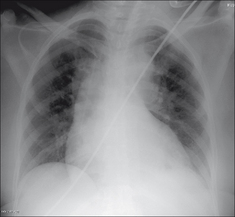

image

Figure 27.2 Female, 38 years. Chest pain. Silhouette sign...pneumonia in the lingular segments of the left upper lobe.